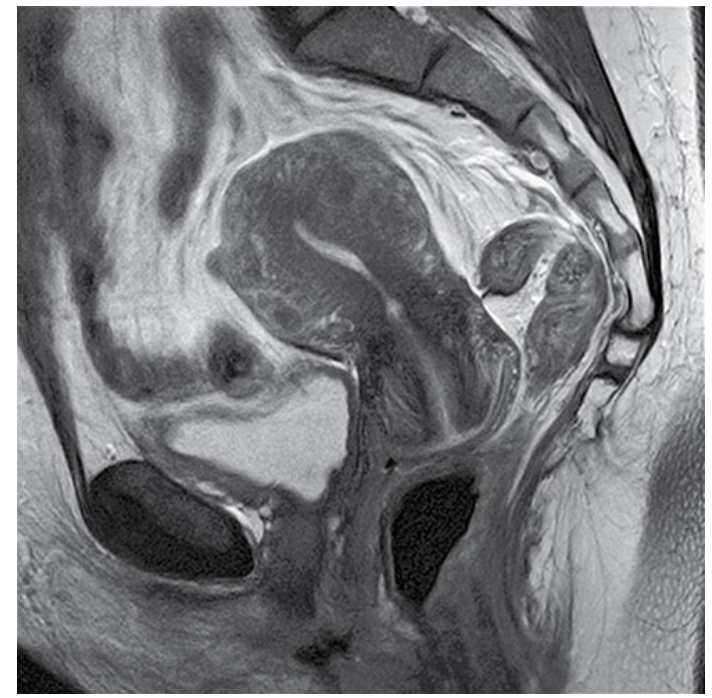

What does this image show?

Sagittal TSE T2-weighted image of a female pelvis